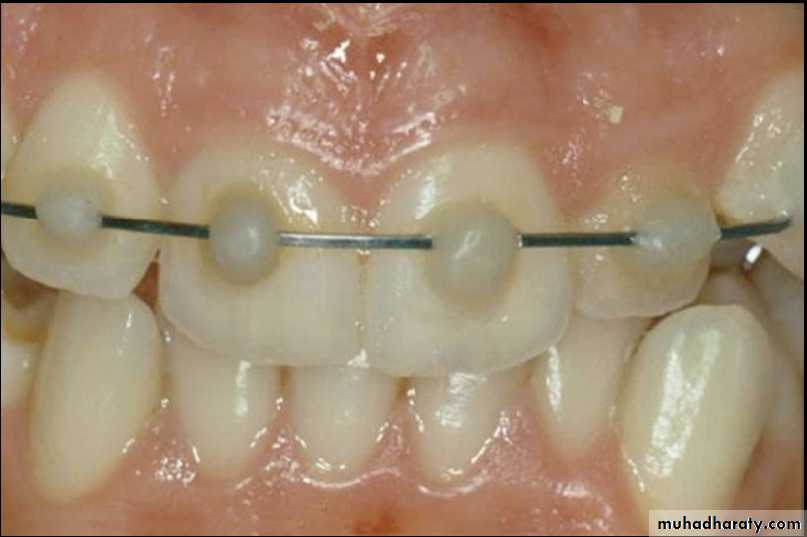

Position of teeth after digital reduction and stabilization with bonded arch wire.- Intrusion

Fixation by wiring

Composite and orthodontic wire splint